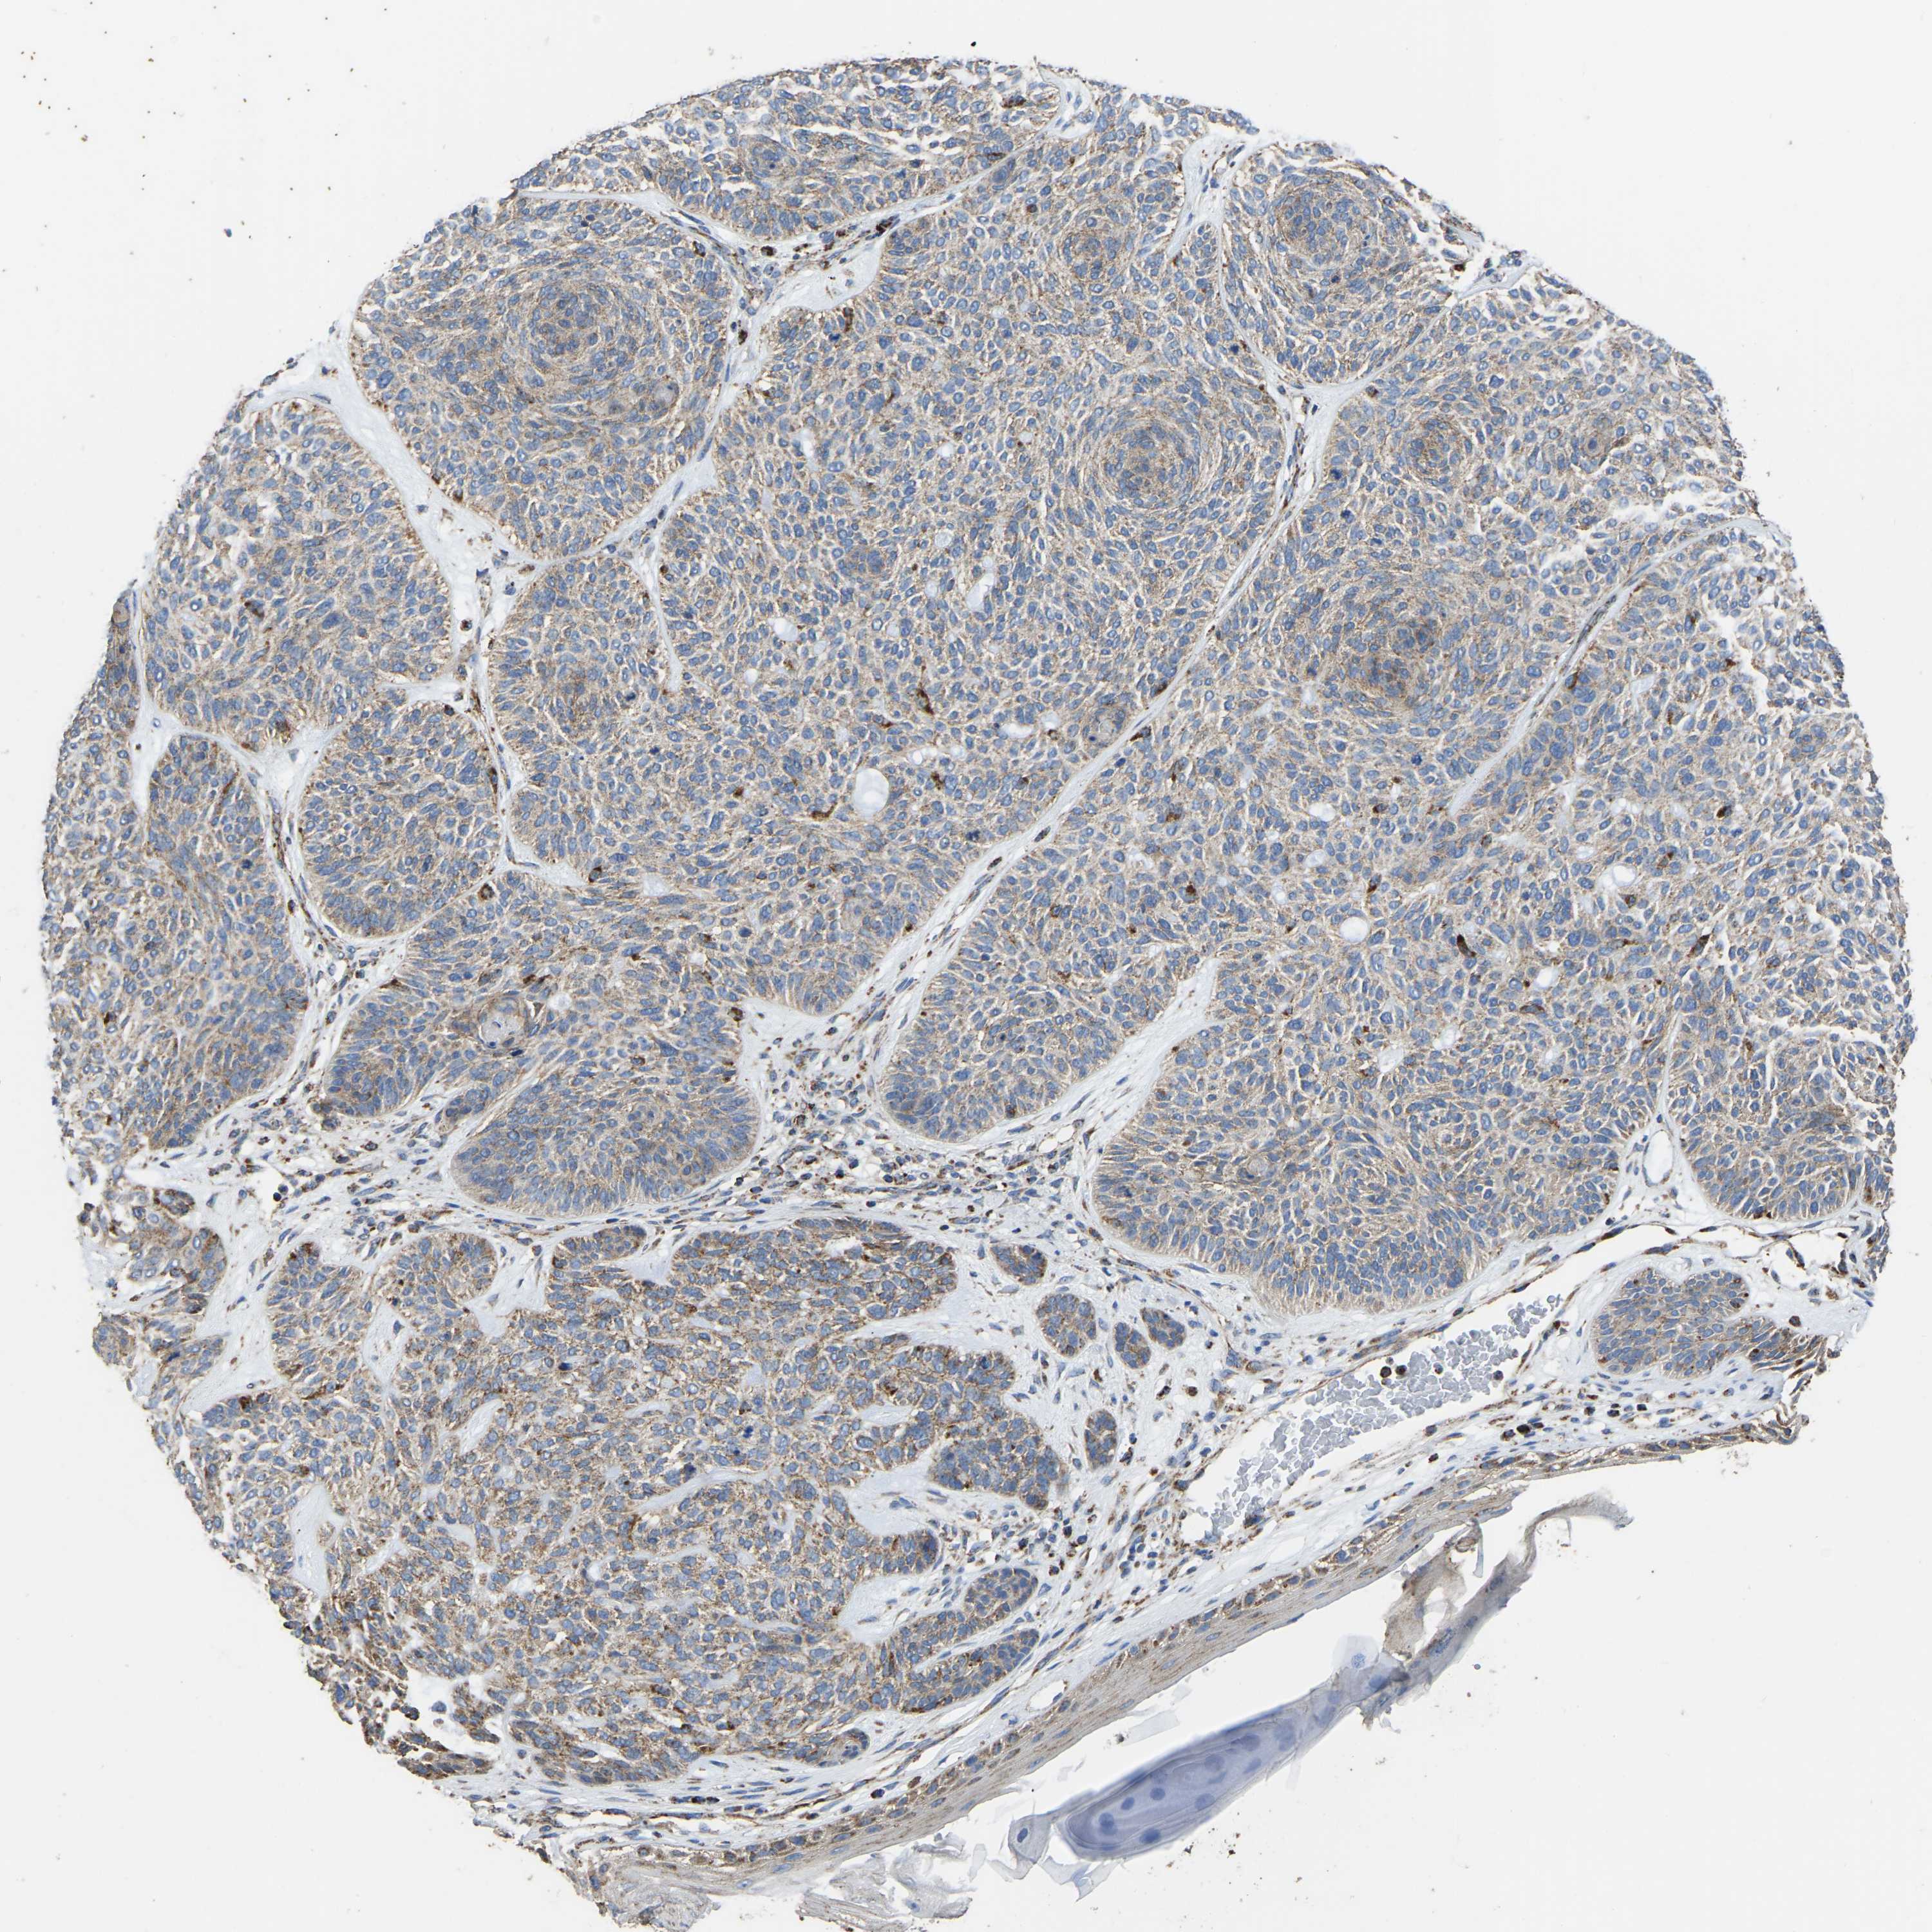

SKIN CANCER - Protein expressioni

A mouse-over function shows sample information and annotation data. Click on an image to view it in a full screen mode. Samples can be filtered based on level of antibody staining by selecting one or several of the following categories: high, medium, low and not detected. The assay and annotation is described here.

Each image is clickable and will lead to virtual microscopy that enables deeper exploration of all samples and also displays staining intensity scores, fraction scores and subcellular localization as well as patient and tissue information for each sample.

Antibody HPA018996

Staining

High

Intensity

Strong

Quantity

>75%

Location

Nuclear

Squamous cell carcinoma, metastatic, NOS